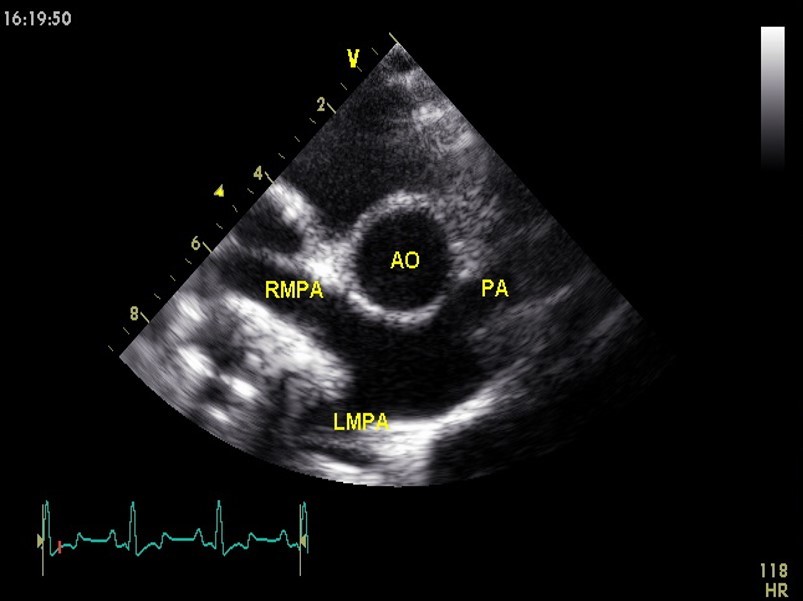

What view and level is this?

Right parasternal short axis @ aortic valve